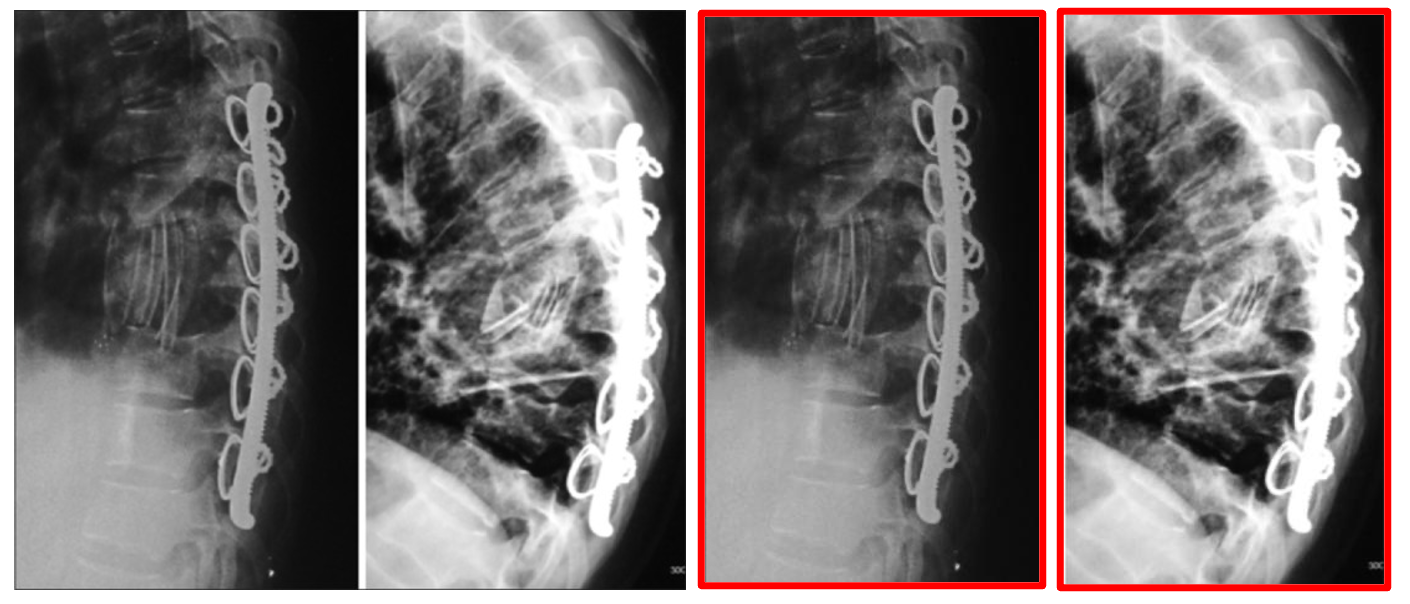

Refer to caption

Figure 1: MedicalNarratives: Here we show 4 samples from the dataset, these samples come from varying videos containing 4 medical modalities, X-ray, CT, MRI, and Histopathology images from left to right. These samples are selected from interleaved samples extracted from source videos, with each sample showing the representative image captured, the raw input text grounded and aligned in-time with the spatial traces & bbox, the denoised medical and ROI text describing the medical image removing all transcription errors, and non-medical information. Please see more examples across all 4 modalities we capture MedicalNarratives for in the Appendix.